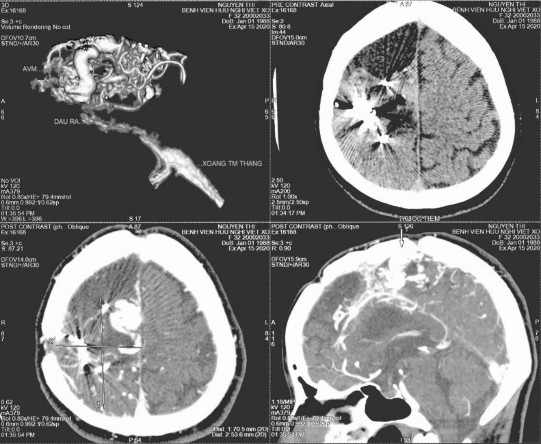

Hình 4.6. Hình ảnh AVM trán trái (bệnh nhân Nguyễn Thị Y. trong nghiên cứu)

Chúng tôi muốn đề cập đến bệnh cảnh của ba trường hợp trong nghiên cứu gồm 01 bệnh nhân sau mổ phẫu thuật u não thái dương trong, 01 bệnh nhân có loạn sản vỏ não thái dương và 01 trường hợp dị dạng mạch não AVM đã can thiệp. Các

bệnh nhân đều được dùng loại thuốc động kinh phù hợp với loại cơn và đủ liều nhưng vẫn còn cơn co giật. Bệnh nhân có phẫu thuật u nang thái dương thuộc nhóm được tư vấn; đã cắt cơn giật trước mang thai 15 tháng, được chỉnh thuốc điều trị trước mang thai 3 tháng, nhưng có cơn giật cục bộ toàn thể hóa tái phát ở quý ba của thai kỳ và khi chuyển dạ nên người bệnh được mổ đẻ cấp cứu. Đối với trường hợp có loạn sản vỏ não thùy thái dương, bệnh nhân còn nhiều cơn cả trước và trong quá trình mang thai, bệnh nhân có cơn động kinh cục bộ phức tạp, hay quên thuốc hoặc tự giảm liều thuốc dù đã được tư vấn trước và trong khi mang thai. Ngược lại, bệnh nhân có tổn thương dị dạng mạch não AVM tuy có nhiều cơn trước mang thai nhưng sau khi được tư vấn chỉnh thuốc, bệnh nhân tuân thủ tốt việc dùng thuốc và thời gian không cơn trước mang thai là 17 tháng. Người bệnh không có cơn giật trong quá trình mang thai và chuyển dạ; đẻ thường đủ tháng an toàn.

Hình 4.8. AVM bán cầu phải sau nút mạch 02 lần (bệnh nhân Nguyễn Thị H. trong nghiên cứu)